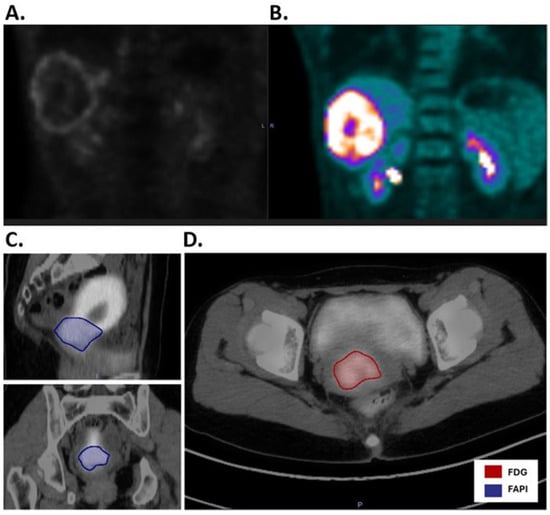

Comparative Evaluation of [68Ga]Ga-Fibroblast Activation Protein Inhibitor vs. [18F]FDG as a Novel Radiotracer for Biology-Guided Image Radiotherapy

by Lin Qiu, Yue Chen, Trevor Ketcherside, Zhixing Wang, Todd DeWees, Terence M. Williams, Arya Amini, Sagus Sampath, Scott Glaser, Yi-Jen Chen, Liu Lin, David Leung, An Liu and Heather M. McGee

Cancers 2025, 17(22), 3648; https://doi.org/10.3390/cancers17223648 - 13 Nov 2025

Background/Objectives: Biology-guided radiotherapy (BgRT) is a novel technology utilizing PET radiotracer emissions to deliver image-guided adaptive RT. 18F-Fluorodeoxyglucose ([18F]FDG) is the most common PET radiotracer but has background in the liver and brain because it is taken up by viable tumor [...] Read more.

Background/Objectives: Biology-guided radiotherapy (BgRT) is a novel technology utilizing PET radiotracer emissions to deliver image-guided adaptive RT. 18F-Fluorodeoxyglucose ([18F]FDG) is the most common PET radiotracer but has background in the liver and brain because it is taken up by viable tumor cells as well as inflammatory cells. Fibroblast activation protein (FAP) is overexpressed in cancer-associated fibroblasts with minimal expression in normal tissues. FAP inhibitors (FAPIs) bind to FAP, and a FAPI labeled with Gallium-68 (68Ga) is a novel radiotracer with high tumor selectivity. Multiple studies have compared [68Ga]Ga-FAPI-04 vs. [18F]FDG for diagnostic imaging, but [68Ga]Ga-FAPI-04 vs. [18F]FDG have never been compared in terms of their utility for BgRT. Purpose: This study was designed to assess the utility of [68Ga]Ga-FAPI-04 vs. [18F]FDG for BgRT used to treat pancreatic, liver, lung, head and neck, and cervical cancers. Methods: A radiation oncologist specializing in each cancer contoured the gross tumor volume (GTV) on [18F]FDG PET-CT and [68Ga]Ga-FAPI-04 PET-CT images. Auto-contours were generated using an auto-threshold of 40% of the maximum Standardized Uptake Value (SUV). The suitability of [68Ga]Ga-FAPI-04 vs. [18F]FDG for BgRT was evaluated by comparing Normalized Net Activity Concentration (NNA) and Normalized Target Signal (NTS) for each cancer. Results: NNA and NTS for [68Ga]Ga-FAPI-04 and [18F]FDG met the requirements for [18F]FDG-guided BgRT (NNA > 5.0 kBq/mL, NTS > 2.7) for all disease sites. NNAFAPI was significantly greater than NNAFDG for pancreatic, H&N, and cervical cancer. NTSFAPI was significantly greater than NTSFDG for pancreatic, liver, and lung cancer. Conclusions: [68Ga]Ga-FAPI-04 is a novel radiotracer for BgRT and has the greatest potential impact in the treatment of pancreatic cancer. Full article